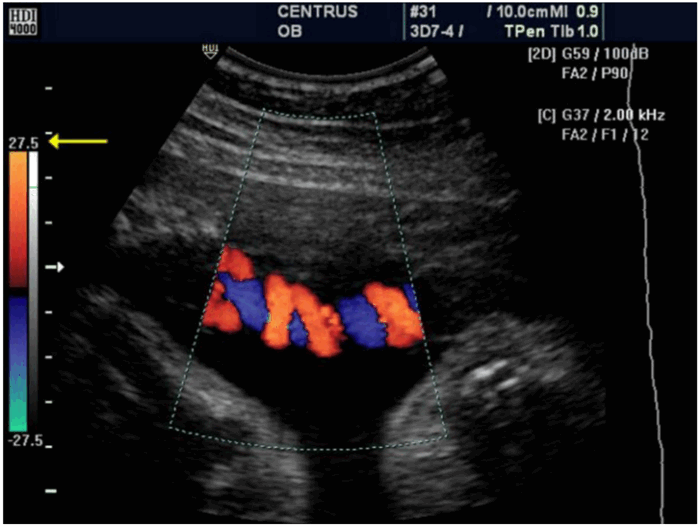

Рисунок 7 (a, b): Цветное допплеровское картирование: влияние частоты повторения импульсов или масштаба цветовой шкалы. а. Установленная низкая частота повторения импульсов, то есть неверный масштаб (отмечен желтой стрелкой). На изображении присутствуют искажения и посторонний шум в пределах контрольного объема пупочной артерии и вены. b. Частота повторения импульсов установлена корректно - масштаб шкалы верный. Цветное изображение показывает артерии и вены четко и без артефактов.

Цветовая допплерография - это импульсноволновой режим допплеровского исследования, при котором на двумерное изображение сердца или сосуда одновременно накладывается большое количество маленьких контрольных объемов, которые распределены по всему двумерному изображению среза сердца или сосуда. Таким образом, в реальном масштабе времени отображается пространственное распределение различных по направлению и величине скоростей потока крови, кодируемых цветом.

б) Кодировка цветом. Для наглядности в этом режиме различные скорости отображаются не в цифровом виде, а разными цветами. При этом скоростям, вектор которых направлен в сторону датчика, соответствуют красно-желтые тона, а скоростям, направленным в сторону от датчика, - сине-голубые. Как и импульсно-волновая допплерография, цветовое допплеровское исследование из-за феномена Найквиста также не может однозначно определять высокие скорости кровотока.

Технологический режим, при котором дуплексное сканирование проходит с использованием цветного допплеровского картирования, называется триплексным сканированием. Цветовой режим дает информацию о качественном состоянии кровотока, его характере (равномерный или турбулентный, с множественными завихрениями), а спектральный режим – количественную, или информацию о скорости кровотока.

Цветовой режим дает более точную оценку проходимости сосудов. Исследуется состояние как венозных, так и артериальных сосудов. Красный цвет на мониторе показывает кровоток, направленный в сторону датчика, синий – направление кровотока от датчика.